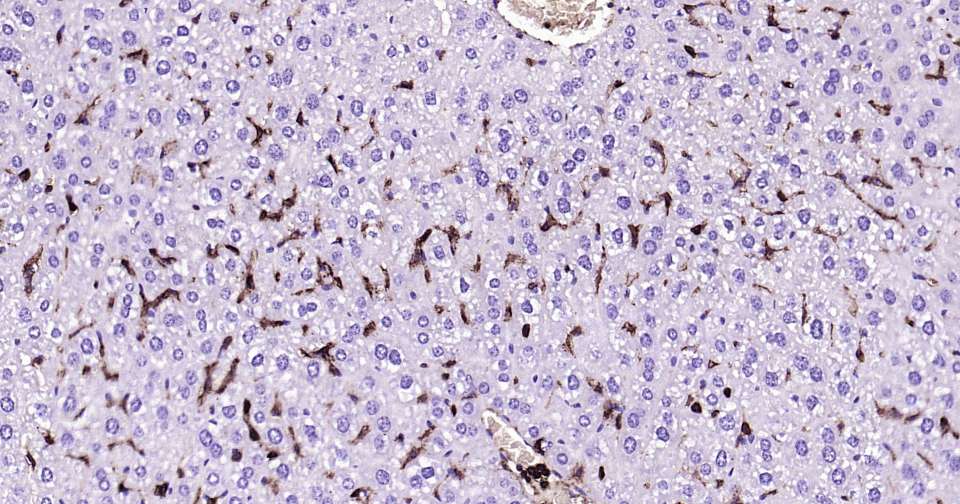

Immunohistochemical analysis of paraffin embedded mouse liver tissue slide using IHC0353M (Human CD44 Kit).